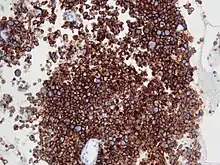

| Micrograph of an anaplastic large-cell lymphoma. H&E stain. | |

ALCL is defined based on microscopic histopathological examination of involved tissues which shows the presence of at least some ALCL-defining pleomorphic cells. These "hallmark" cells have abnormal kidney-shaped or horseshoe-shaped nuclei, prominent Golgi, and express the CD30 tumor marker protein on their surface membranes.[4] In 2016, the World Health Organization (WHO) separated ALCL into four types: ALK-positive ALCL (also termed ALK+ ALCL), ALK-negative ALCL (ALK− ALCL), primary cutaneous ALCL (pcALCL), and breast implant-associated ALCL (BIA-ALCL). WHO defined BIA-ALCL as an ALCL type provisionally, i.e. subject to redefinition if future studies should support such a change.[4][5]

ALK-positive ALCL is diagnosed by histological and immunological examinations of involved tissues, typically lymph nodes. These tissues have lymphoma-like infiltrates that have variable numbers of ALCL "hallmark" cells, i.e. cells with kidney- or horseshoe-shaped nuclei that strongly express CD30 as detected by immunohistochemistry and an ALK fusion protein as detected by fluorescence in situ hybridization.[11] These cells are scattered throughout the infiltrates. WHO classifies these infiltrates into 5 patterns: a common pattern consisting of large variably shaped cells with large nuclei that typically contain multiple nucleoli (60–70% of cases); a small-cell pattern consisting of small to medium-sized neoplastic cells with clear cytoplasm and "hallmark" cells that are concentrated around small blood vessels (5–10% of cases); a lymphohistiocytic pattern consisting of small neoplastic cells along with abundant histiocytes (10% of cases); a Hodgkin's-like pattern in which the architecture resembles the nodular sclerosis pattern of Hodgkin lymphoma (3% of cases); and a composite pattern consisting of two or more of the just described patterns (15% of cases).[9] Detection of circulating autoantibody against ALK supports the diagnosis.[10] Individuals with low levels of these autoantibodies are at an increase risk of relapsing after treatment.[9]

The histology of ALK-negative ALCL, similar to ALK-positive ALCL, consist of "hallmark" cells that strongly express CD30. Unlike ALK-positive ALCL, however, ALK-negative ALC does not fall into different morphological patterns. The histological of this disease may overlap with and be difficult to distinguish from other CD30-positive T-cell lymphomas or the nodular sclerosis form of Hodgkin lymphoma. Cases in which ALK-negative ALCL is not distinguishable from the latter lymphomas are best diagnosed as peripheral T-cell lymphoma not otherwise specified (PTL, NOS). The histology of ALK-negative ALCL may also overlap with tumors of non–T-cell lineage such as various carcinomas. The differential diagnoses of ambiguous cases may be helped by examining the tumor cells for the expression of certain marker proteins. For example, expression of CD56, MUC1 (also termed EMA for epithelial membrane antigen), and clusterin and strong uniform expression of CD30 support the diagnosis of ALK-negative ALCL over PTL, NOS, while variable CD30 expression and extensive expression of T-cell receptor proteins favor PTCL-NOS over ALK-negative ALCL. Detection of certain gene abnormalities (see next section) may also help distinguishing these diseases.[4]

Diagnosis

In most individuals with BIA-ALCL, the affected breast has a thickened capsule around the implant and effusion fluid between the capsule and implant. Neoplastic cells are located in and typically limited to the capsule and effusion. Histological examination of the capsules shows large anaplastic cells but cells with all the features of ALCL "hallmark" are often difficult to detect. In addition to these neoplastic cells, the capsule lesions contain, sometimes in a large excess that makes diagnosis difficult, a variety of non-malignant cells such as small lymphocytes, histiocytes, and granulocytes (the granulocytes are mostly eosinophils). The histology of palpable masses exhibit a different pathological picture: the tumor masses have multinodular areas that consist of necrosis or fibrous tissue interspaced with areas that consist of large neoplastic cells that have abundant cytoplasm and abnormally shaped nuclei within a fibrotic and chronic inflammatory cell background. Again, typical ALCL-defining "hallmark" cells may be difficult to find in these masses. The effusions show abundant, uniform-appearing, non-cohesive large cells with irregularly-shaped nuclei, prominent nucleoli and abundant cytoplasm.[27] The histology and pathological features of diseased lymph nodes and tissues outside of the breast implant are indistinguishable from those seen in ALK-negative ALCL. The neoplastic cells in the capsules, effusions, and tissues strongly and uniformly express CD30, CD4 (75–84% of cases), EMA (48–90%), CD43 (86–95%), CD45 (44–74%), and in a far fewer percentage of cases various other marker proteins. These cells do not express ALK and often lack the characteristic surface marker proteins of T-cells. Identification of the status of these markers helps diagnose the disease.[4]